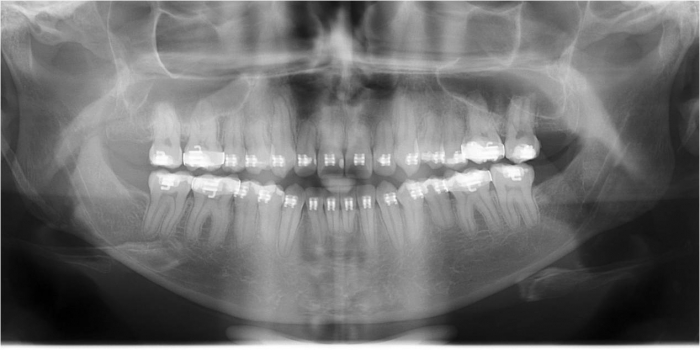

Raio x inicial